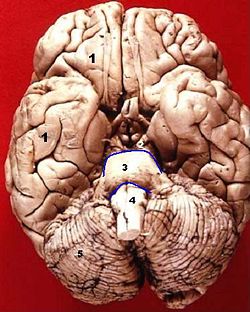

| Inferior view mesencephalon (2), above (3) | ||

فى علم التشريح فإن ال, mesencephalonأو ( دماغ متوسط) يشمل tectum (أو corpora quadrigemini), tegmentum, the ventricular mesocoelia أو( "iter"), و الcerebral peduncles, بالإضافة الى العديد من nuclei و fasciculi. Caudally ال mesencephalon يرتبط ب pons (metencephalon) و يرتبط ب diencephalon (Thalamus, hypothalamus, et al).

Cerebral Peduncle

The cerebral peduncles are paired structures, present on the ventral side of cerebral aqueduct, and they further carry tegmentum on the dorsal side and cresta or pes on the ventral side, and both of them accommodate the corticospinal tract fibres, from the internal capsule (i.e ascending + descending tracts = longitudinal tract.) the middle part of cerebral peduncles carry substantia nigra (also called "Black Matter") which is a type of basal nucleus. It is the only part of the brain that carries melanin pigment.

Between the peduncles is the interpeduncular fossa, which is a cistern filled with cerebrospinal fluid. The occulomotor nerve comes out between the peduncles, and the trochlear nerve is visible wrapping around the outside of the peduncles.